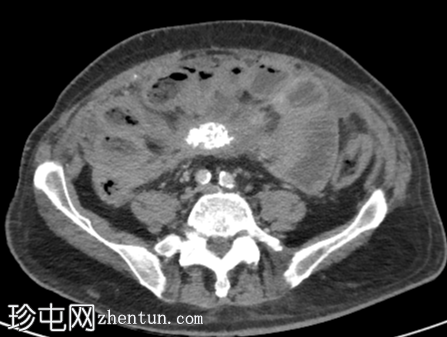

轴位增强扫描(门静脉期)

肠系膜可见一软组织密度增高的肿块,大小为34 x 67 mm,部分钙化,边缘呈毛刺状,牵拉多个小肠袢,提示存在促纤维增生反应。

肠系膜上动脉(SMA)与该肿块关系密切。

肠系膜充血和肠壁增厚。近端小肠轻度扩张。

根据大小标准,未见腹盆腔淋巴结肿大。

右下腹可见腹膜结节,最大结节大小为28 x 19 mm。

大网膜呈结节状增厚。

少量腹水和胸腔积液。

未见其他转移。

未发现疑似小肠原发肿瘤

显著的动脉粥样硬化、多发性小肾梗死和非梗阻性结石。